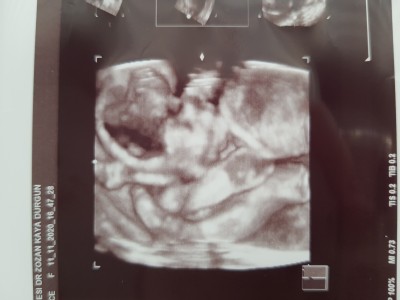

Kizlar fotografta gorundugu gibi bebegimin poposu asagida kafasi ve ayaklari yukarda birleşmiş sanki sıkışmış  gibi, ilk defa boyle goruyorum, doktor da biraz tuhaf durmus ama o sekil degistirir dedi surekli ama hic icime sinmedi sanki sikismis gibi, normal mi sizce hic bebegi boyle pozisyon alan oldu mu? O kadar ultrason goruntusu bakiyorum hic boyoe görmedim.

Gebelik haftası 24+2